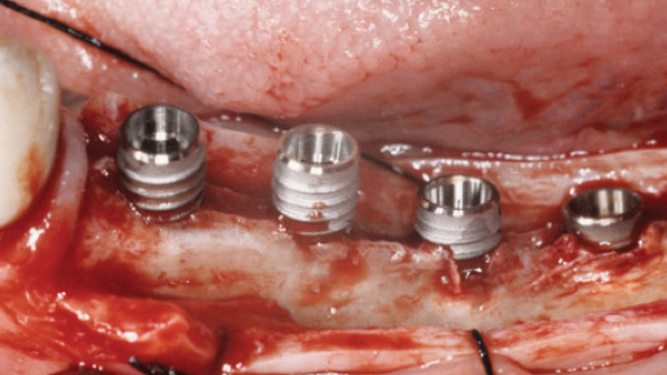

“Thin ridge expansion with minimally invasive surgery!

Use SmarThor & AnyRidge to place a wider diameter implant with minimal drilling after ridge splitting, even in thin ridge under 2mm! “

Clinical case: Ridge splitting technique using SmarThor + AnyRidge as expander

- Courtesy of Dr.Kwang-Bum Park, Korea -

Keywords

AnyRidge, ridge splitting, GBR, Dr. Kwang-Bum Park, mandibular posterior, SmartThor, Mega-Oss, thin ridge, bone regeneration

Products:

AnyRidge implant system. SmarThor, Mega-Oss